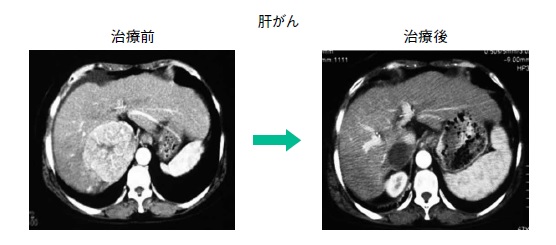

治療対象はIMRTとほぼ同じですが、頭頸部がん等でIMRTでは治療困難な、腫瘍の近くに重要臓器があるような鼻腔・副鼻腔のがんや肝細胞がん(図2)、食道がん、前立腺がん、骨軟部腫瘍、肺がんではⅢ期の一部、とくに縦隔リンパ節転移のある例も対象となります (化学療法と併用)。